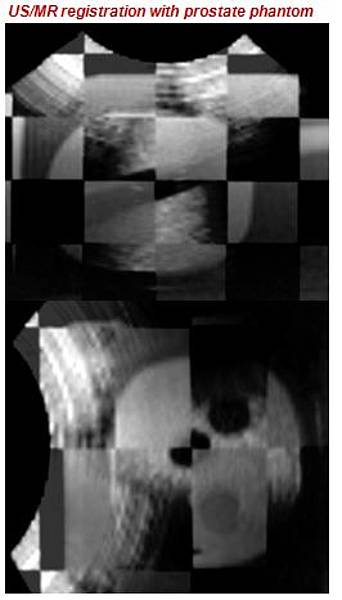

Multi-modal image registration aims to spatially align medical images from different imaging modalities into the same coordinate space. Image fusion through registration can integrate complementary information from multi-modal imagesto help achieving more accurate diagnosis and treatment. This is useful in minimally or non-invasive procedures such asimage-guided surgery, guided radiotherapy planning and image-guided biopsy where diagnostic information from pre-operativeimages (Computed tomography (CT), Magnetic resonance (MR) or Positron-emission tomography (PET)) are fused withintra-procedural imaging (e.g. ultrasound (US)).

The idea of this project was to develop a real-time navigation system which allows for image fusion between two arbitrary image modalities by replacing the (commonly used) inter-modal registration by an intra-modal 3D-US/3D-US registration and the use of an optical tracking system (OTS). This should avoid well know difficulties arising from inter-modal registration. Such challenges are described for a large variety of modalities. For example, in multi-modality image-guided prostate biopsies, the registration between MR and transrectal-US (TRUS) images is difficult due to the poor signal to noise ratio and lack of well-defined features in US images and the inhomogeneous imaging resolutions. Therefore, the registration is commonly performed using surface-based methods, utilizing image segmentation to address the appearance difference between the two modalities.